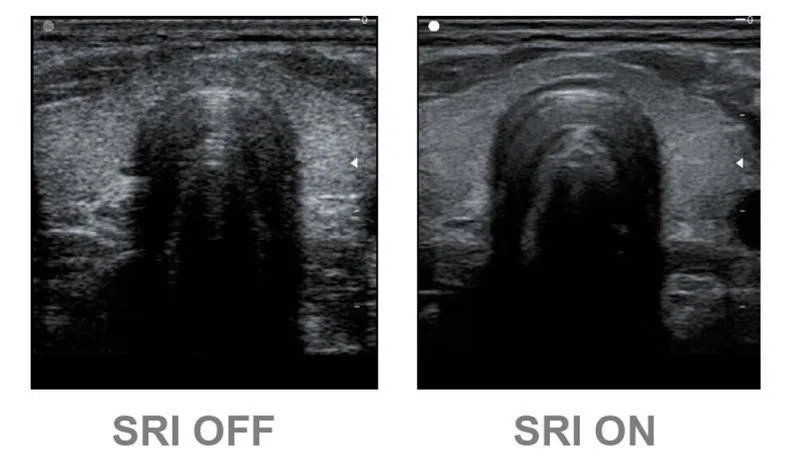

Speckle Reduction Imaging (SRI) - технология значительно снижает количество нежелательных пятен и зернистости. В результате фильтрации улучшается связь между неоднородными участками тканей различных органов, значительно увеличивается пространственное и контрастное разрешение. Эхограмма становится более легкой для «чтения» за счет повышения качества визуализации контуров, структур тканей и мелких деталей.